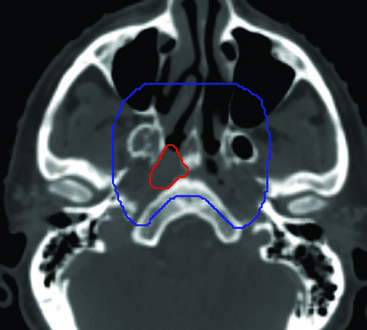

El volumen subclínico (CTV54-59.4) del carcinoma nasofaríngeo es, posiblemente, el más complejo de toda la cabeza y el cuello. Debe englobar no solo el GTV con un margen de 10 mm, sino también la nasofaringe completa, el paladar blando, la cavidad nasal posterior (al menos 5 mm anteriores a las coanas), la porción posterior de los senos maxilares —incluyendo la fosa pterigopalatina y el trayecto de V2—, los senos etmoidales posteriores y los forámenes de la base del cráneo.

La extensión craneal del CTV subclínico varía según el estadio T:

- T1-T2: Mitad del seno esfenoidal, tercio anterior del clivus.

- T3-T4: Seno esfenoidal completo, clivus completo, seno cavernoso y cavidad de Meckel.

Los espacios pterigoideos y parafaríngeos se incluyen siempre. La revisión de la ventana ósea en la TC de planificación es mandatoria para identificar los forámenes oval, redondo mayor y rasgado anterior. La erosión sutil de estas estructuras puede pasar desapercibida en ventana de partes blandas.

Caso 2: T4N2 EBV positivo

Paciente con enfermedad localmente avanzada, extensión intracraneal a través del foramen oval y seno cavernoso ipsilateral, adenopatías bilaterales en niveles II-V. El GTV70 incluyó el tumor primario con toda su extensión intracraneal visible en RM T1 con gadolinio, así como el conglomerado ganglionar necrótico. El CTV70 se expandió 5 mm en la mayoría de las direcciones, reduciéndose a 0 mm en la interfaz con el lóbulo temporal. El CTV subclínico requirió la inclusión del seno esfenoidal completo, el clivus completo, la cavidad de Meckel bilateral y todos los niveles cervicales bilaterales hasta la grasa posterior a la clavícula en el nivel V.